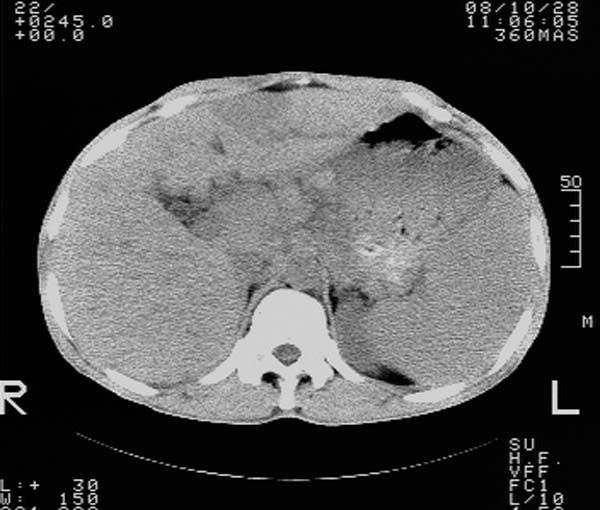

m,65y。半年前发现颈小结节,逐渐增多增大,现双侧耳后、颌下及颈部表浅淋巴肿大。胸片示双肺门增大。外院曾穿刺诊断为淋巴结核。在我科作胸腹部ct,我们觉得外院病检有误。现将图像上传请战友讨论。

纵隔内及腹膜后广泛淋巴结肿大,脾大,肝内似可见低密度影,结合病史半年前发现颈小结节,逐渐增多增大,现双侧耳后、颌下及颈部表浅淋巴肿大。考虑淋巴瘤。

我们也是首先考虑淋巴瘤。只是外院病检报告是结核。让人迷惑。肝左叶多发低密度占位,没增强不好定论。

纵隔,双肺门腹膜后多发淋巴结重大,非融合,肝脾轻度肿大,双肺野弥漫性小结节;考虑淋巴瘤,结节病可能性

纵隔内,双肺门、腋窝及腹膜后多发肿大淋巴结影,肺内小结节影,肝脾体积增大,支持淋巴瘤。肝内多发低密度影,考虑小囊肿。

考虑淋巴瘤肺、肝内转移,脾脏肿大。

纵隔内,双肺门、腹膜后多发肿大淋巴结影及颈部淋巴结肿大,肝脾体积大.结合临床,淋巴瘤可能性大。